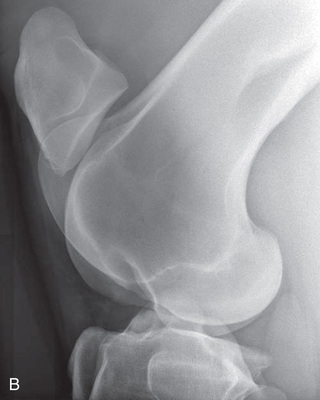

To attain quality projections of the shoulder joint, the use of general anesthesia and placement of the patient in lateral recumbency are recommended. The standing position may be possible if the patient tolerates manipulation. The easiest and maybe only view of the shoulder that can be obtained is the mediolateral.

Shoulder Optional views | Mediolateral (ML) | Lateral (L) |

| Cranioproximal 45-degree medial–caudodistolateral oblique (CrPr45M-CaDiLO) | CrMCdLO | |

| Cranioproximal 45-degree lateral–caudodistomedial oblique (CrPr45L-CaDiMO) | CrLCdMO | |